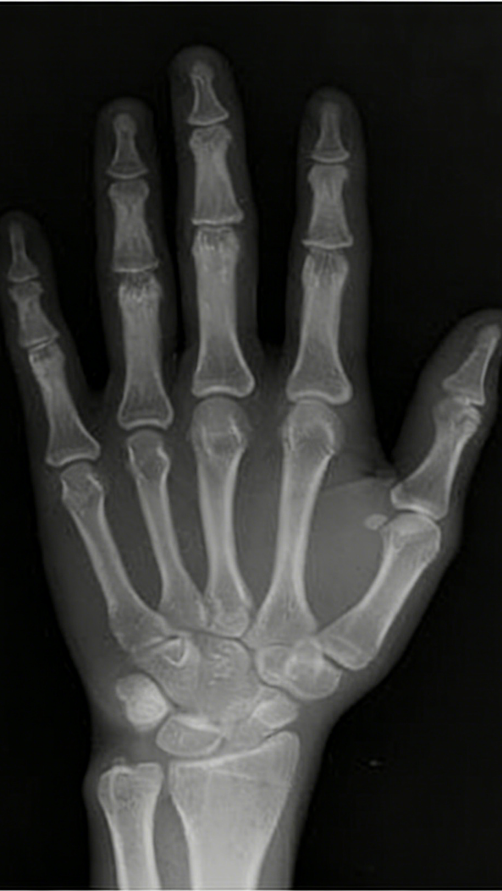

通过拍摄左手腕骨 X 光片,观察骨骺闭合状态是最准确的判断方式。

如果 X 光片显示骨骺线未闭合,说明仍有生长潜力;若已完全闭合,则身高基本定型。即使孩子实际年龄较小,但骨龄超前且接近闭合,生长空间也会受限。

图注:左图,骨骺未闭合;右图:骨骺已闭合